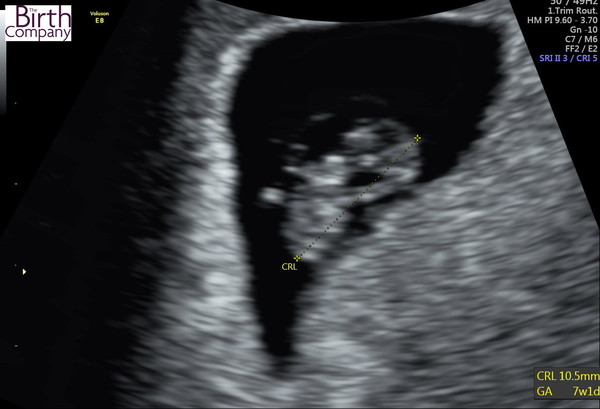

@baby160P Here is a pic. My baby at 7+1 was just over 1cm

This is mine 7 week exact.

@ladycarlotta I guess if the 1mm thing is true then in makes sense I was 9.77mm and French gal is a day ahead at just over 1cm. Mad!!!!

My scan last Friday when I was measuring at 5+5 the baby was 3mm. Hoping it’s much larger and has a heartbeat tomorrow x

@FrenchGal and @Baby160p - did you both see heartbeats then on the 7 week scans? I will be 7+2 on Sunday.

@SuperSharpShooter82 strong heartbeat at 144bpm. Such a special moment

Yes I saw the heart beat at 7 weeks exactly.